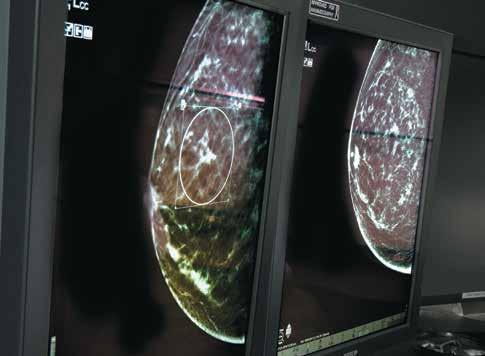

3D imaging improves biopsy process

Emory inaugurated 3D mammography, or digital breast tomosynthesis (DBT), imaging technology for regular screening mammograms because it is more accurate at detecting breast cancers and produces fewer false-positives that result in patient call-backs. But when a woman is called back and additional mammograms show something that could be cancer, the next step is a biopsy to sample a tiny bit of tissue from the suspected area. Every stage of this process, and any subsequent treatment, is extremely dependent on accuracy. Now, doctors within Winship’s Glenn Family Breast Center are using 3D technology throughout the screening and biopsy process. Some breast lesions and calcifications may be subtle and visible only on 3D imaging, so using the technology to guide biopsies enables physicians to more accurately pinpoint and mark areas that may prove to be small, treatable breast cancers. The new Affirm 3D biopsy system is being used at Winship breast imaging facilities on Emory’s Clifton Campus, Emory University Hospital Midtown, Emory Johns Creek Hospital, and soon will be at Emory Saint Joseph’s Hospital. W

Michael Cohen is director of Emory Breast Imaging Centers.